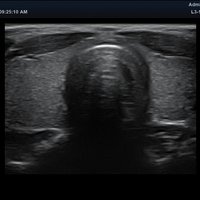

Eigenschaft minisono C1-6 minisono L3-12

Typ konvex linear

Frequenz 1 - 6 MHz 3 - 12 MHz

Maße (Länge/ Breite/ Höhe) 25,5/ 62,5/ 157mm 25,2/ 62,5/ 150mm

Gewicht 5,8 oz/ 175g 5,6 oz/ 165 g

Scan-Tiefe 30 cm 10 cm

Sichtfeld 78 ° 38,4 mm

Display Microsoft Surface Microsoft Surface

Batterielaufzeit 300 min 300 min

Anwendungsbereiche Abdomen MSK, Nerven, Karotis, periphere Gefäße, Schilddrüse, Mamma

Bildgebungs-Modi B-Modus, CF, M, PW, PD B-Modus, CF, M, PW, PD